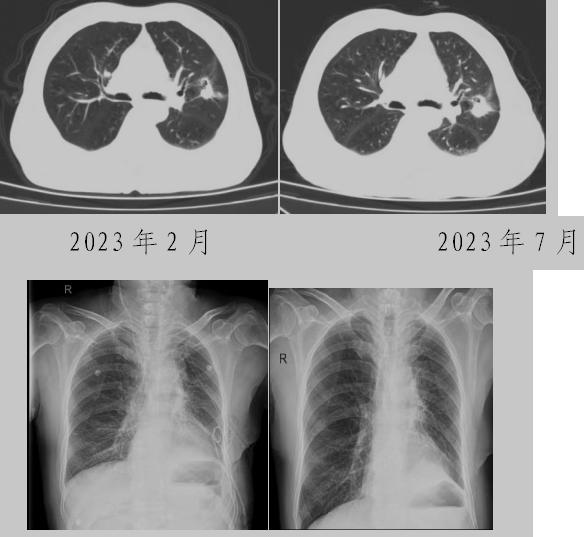

病例一:70多歲的患者王先生于2020年“急性心梗”入院時(shí)檢查發(fā)現(xiàn)了肺部結(jié)節(jié),王先生沒(méi)有在意,其間未規(guī)范復(fù)查胸部影像學(xué)檢查,于2023年2月份再次發(fā)作心絞痛時(shí),發(fā)現(xiàn)肺結(jié)節(jié)已發(fā)展成直徑約2.5cm實(shí)性腫塊,患者在家長(zhǎng)期口服“替格瑞洛及腸溶阿司匹林”等抗凝藥物,生活可自理,于冠狀動(dòng)脈二次植入支架后三個(gè)月,收住市二院胸外科,經(jīng)心內(nèi)科、麻醉科等多學(xué)科會(huì)診后,由胸外科主任王松陽(yáng)、副主任醫(yī)師薛飛及科室團(tuán)隊(duì)行“單孔胸腔鏡下左上肺癌根治術(shù)”,術(shù)后結(jié)合快速康復(fù)理念,三天后拔除胸管,一周出院。